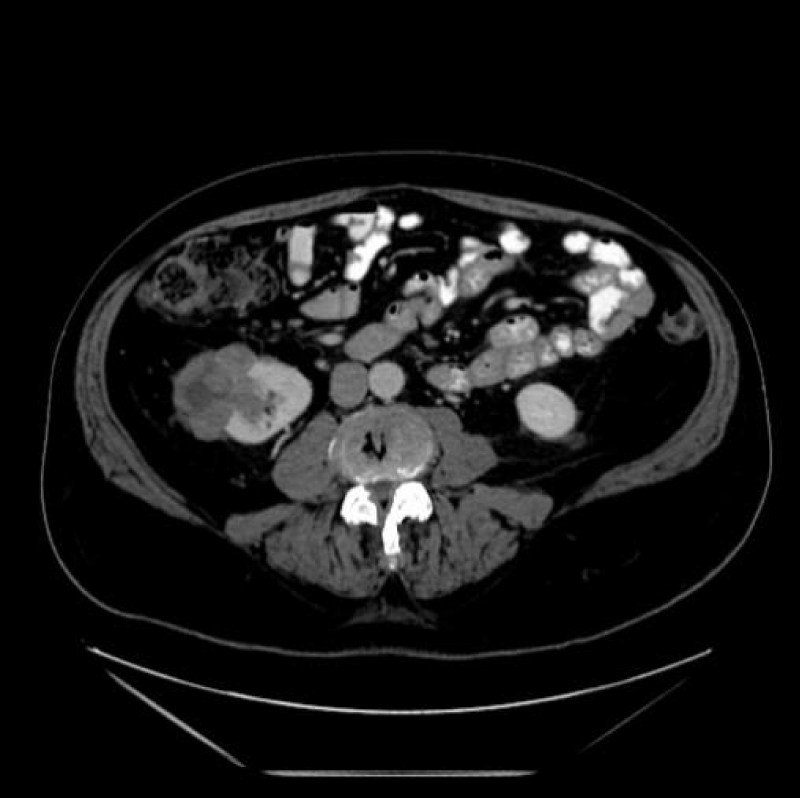

Initial diagnoses and staging are most commonly done with abdominal Computed Tomography (CT), Magnetic Resonance Imaging (MRI) (Figure 1) and Ultrasound (US) are also frequently used. This is due to CT’s ability to detect up to 90% renal masses including SRM, and its higher spatial resolution compared to the MRI. CT can distinguish benign from malignant lesions hence avoiding further testing and detecting surrounding lymphadenopathy or thrombi (Figure 2), has rapid image acquisition rates, is compatible with metallic medical devices, and can obtain high-resolution enhancement measurements using the Hounsfield unit (HU [1-3,5].

Figure 1: T2 Weighted MRI of a multi-Cystic right renal mass.